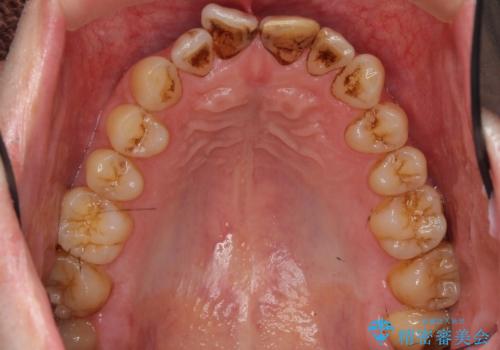

- 前歯のプラスチックの詰め物が気になると来院された患者様です。

左上の前歯に詰められたプラスチック(コンポジットレジン)は、劣化し変色していました。

レジンを除去したところ二次う蝕を認めたため、丁寧に虫歯をとりました。

歯の欠損範囲が大きいことから、同様にレジン修復しても欠けやすいためセラミッククラウンによる補綴を行いました。

患者様のご希望により、最終補綴前にホワイトニングを行いました。